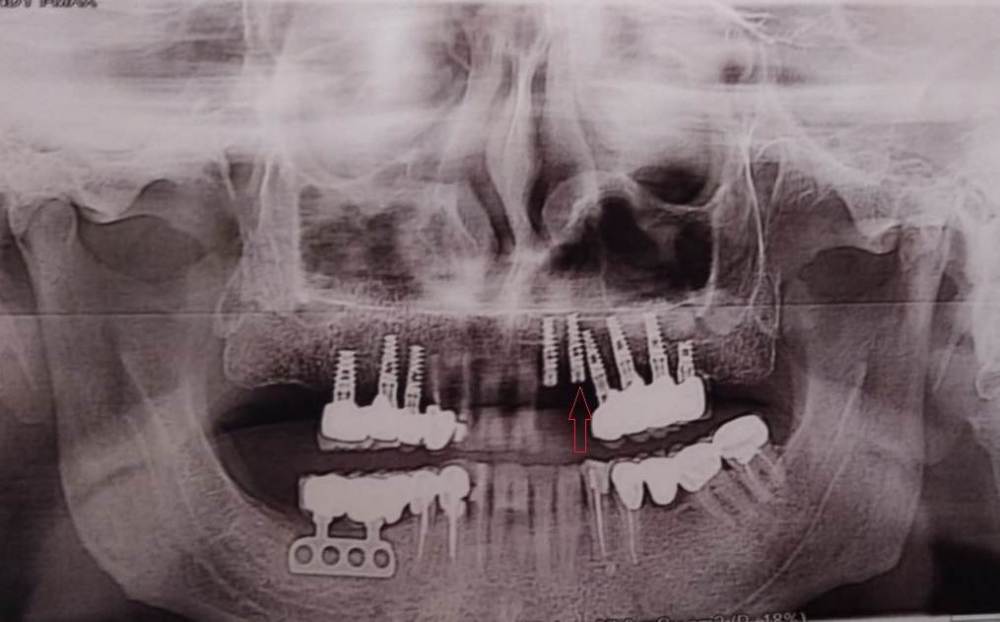

pistons777 Опубликовано 6 декабря, 2023 Поделиться Опубликовано 6 декабря, 2023 Подскажите, пожалуйста, правильность установки импланта (выделенного стрелкой). Интересует близкое расположение к рядом стоящему импланту. Два импланта 22 и 23, были установлены пол года назад. Через 1 - 1.5 месяца после установки, были сняты формирователи десны, по причине, что доктору, что то не понравилось и их места были зашиты. Объяснение было, что нужно исключить любое воздействие при жевании. На данный момент ничего не беспокоит, но хотелось услышать профессиональное мнение. Спасибо! Ссылка на комментарий

АнтонТЛТ Опубликовано 6 декабря, 2023 Поделиться Опубликовано 6 декабря, 2023 Для оценки расстояния между имплантатами нужен трехмерный снимок, по оптг нельзя оценить расстояние в этой области, т.к. челюсть имеет изгиб в районе клыка и может создаваться впечатление, что имплантаты стоят слишком близко друг к другу. 1 Ссылка на комментарий